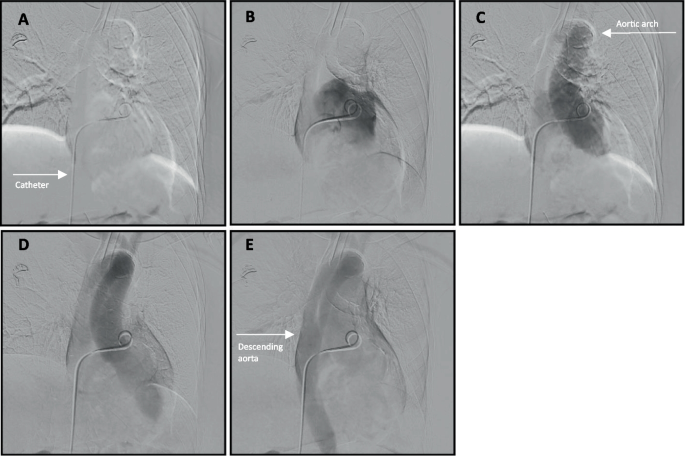

图1

多平面CT图像显示双侧肺动脉充盈缺损(白色箭头所示)